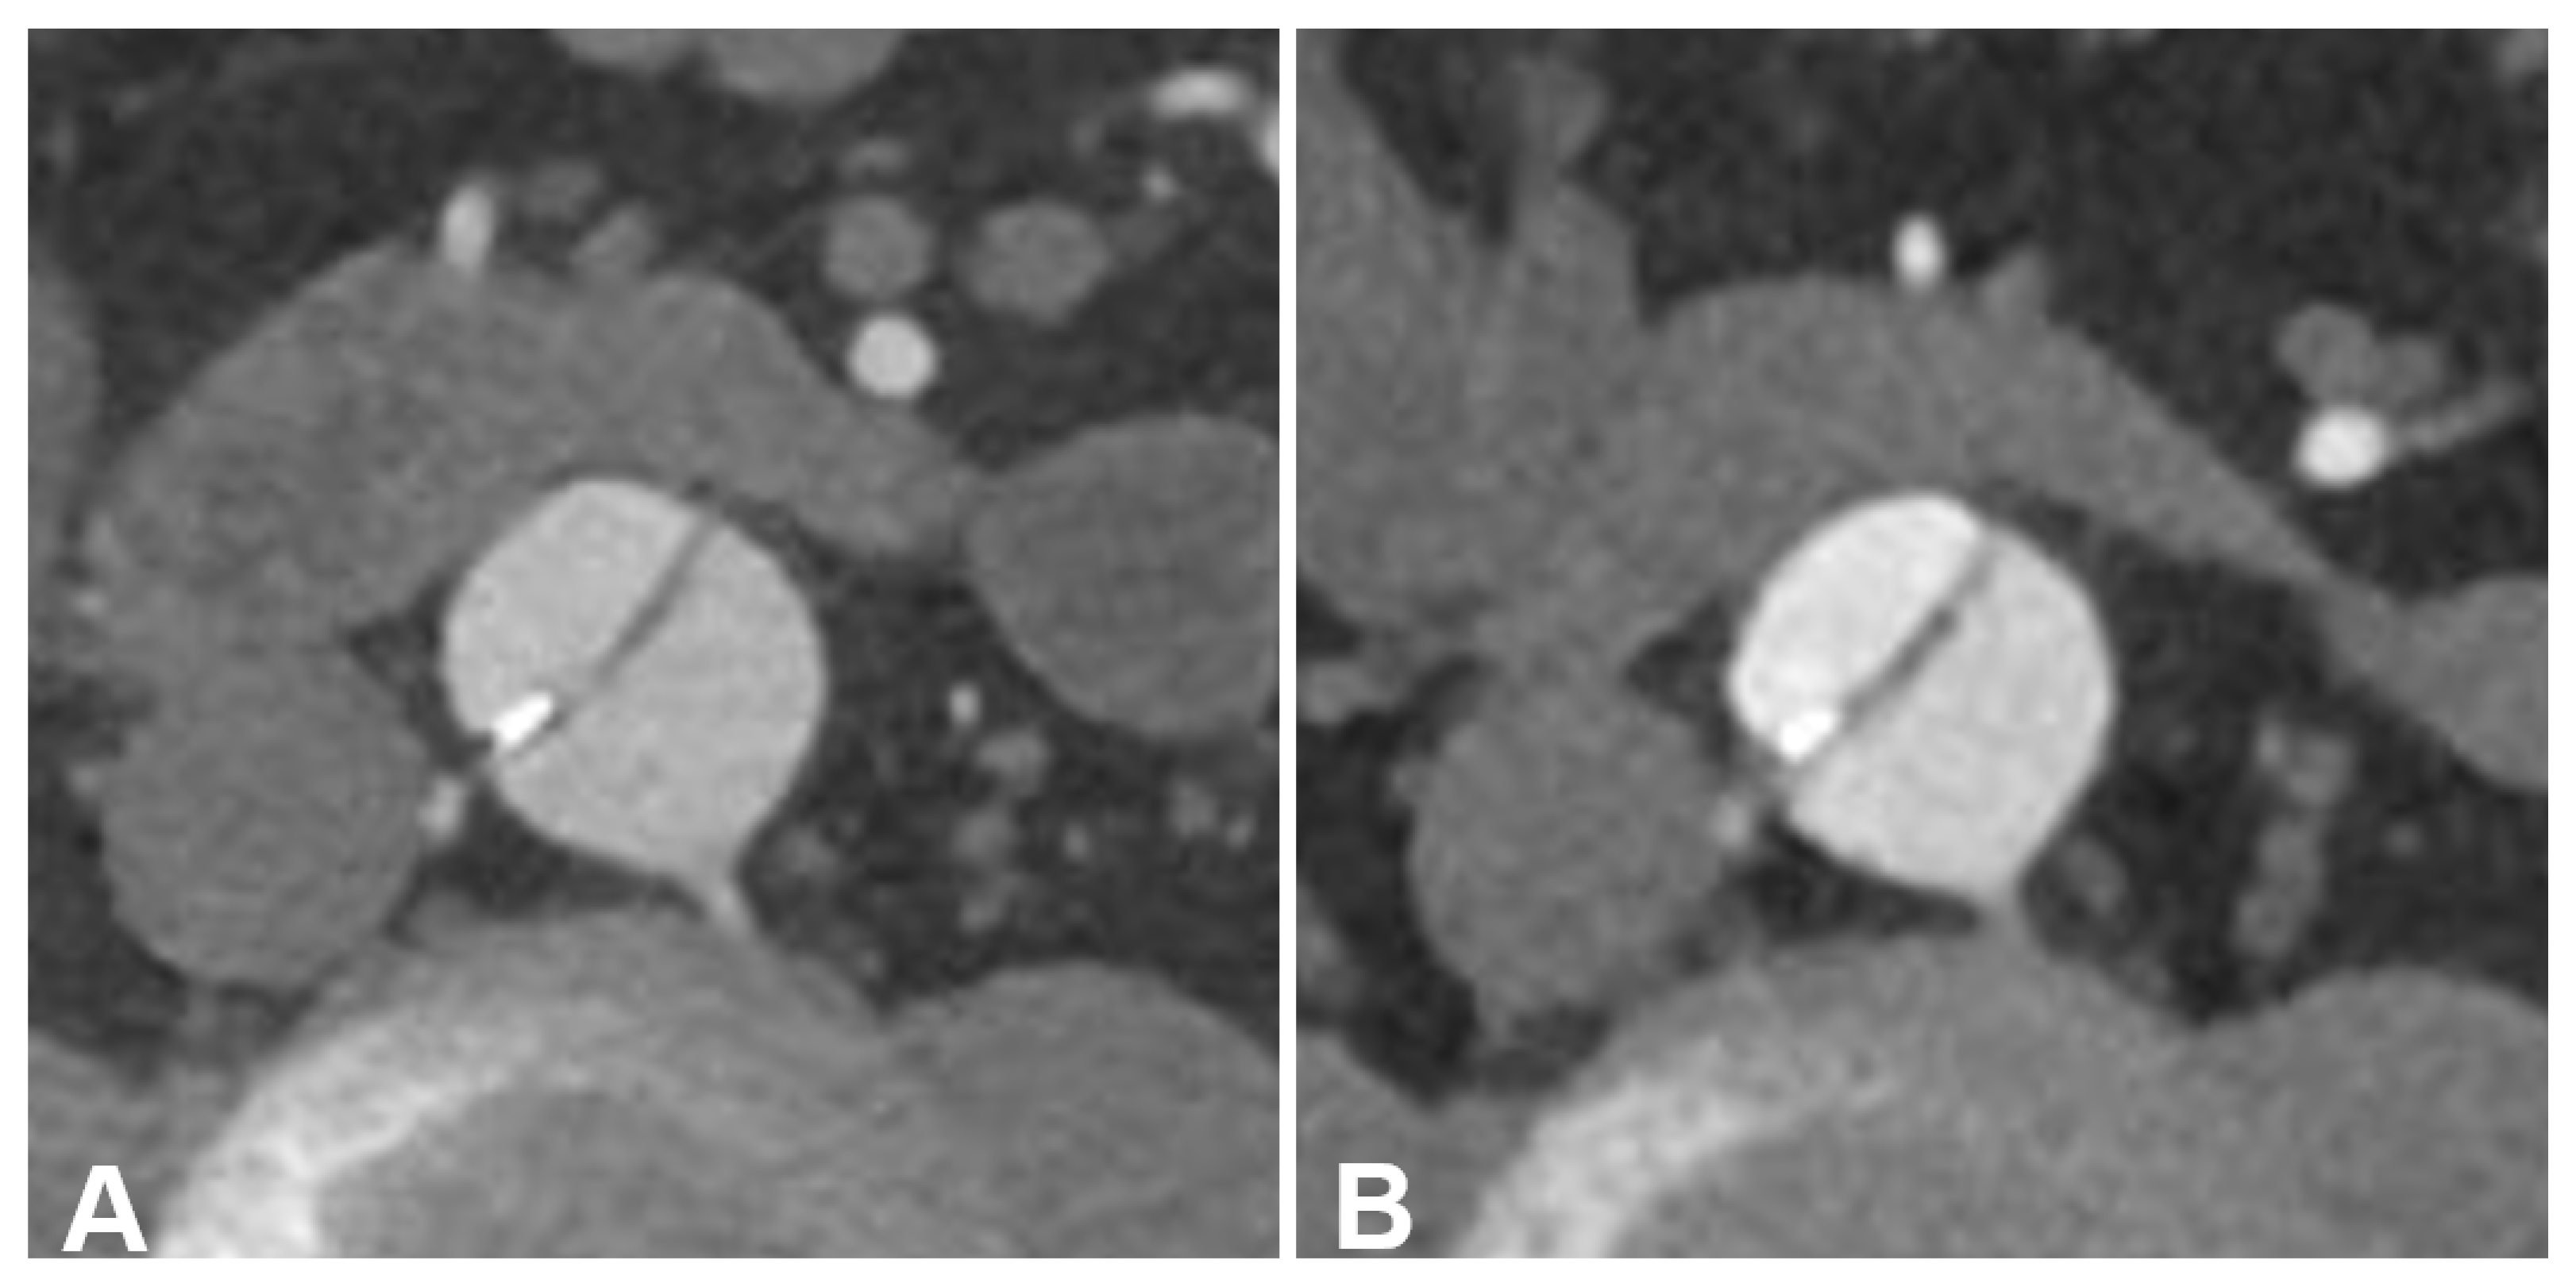

3.3. Subjective Image Quality

4. Discussion